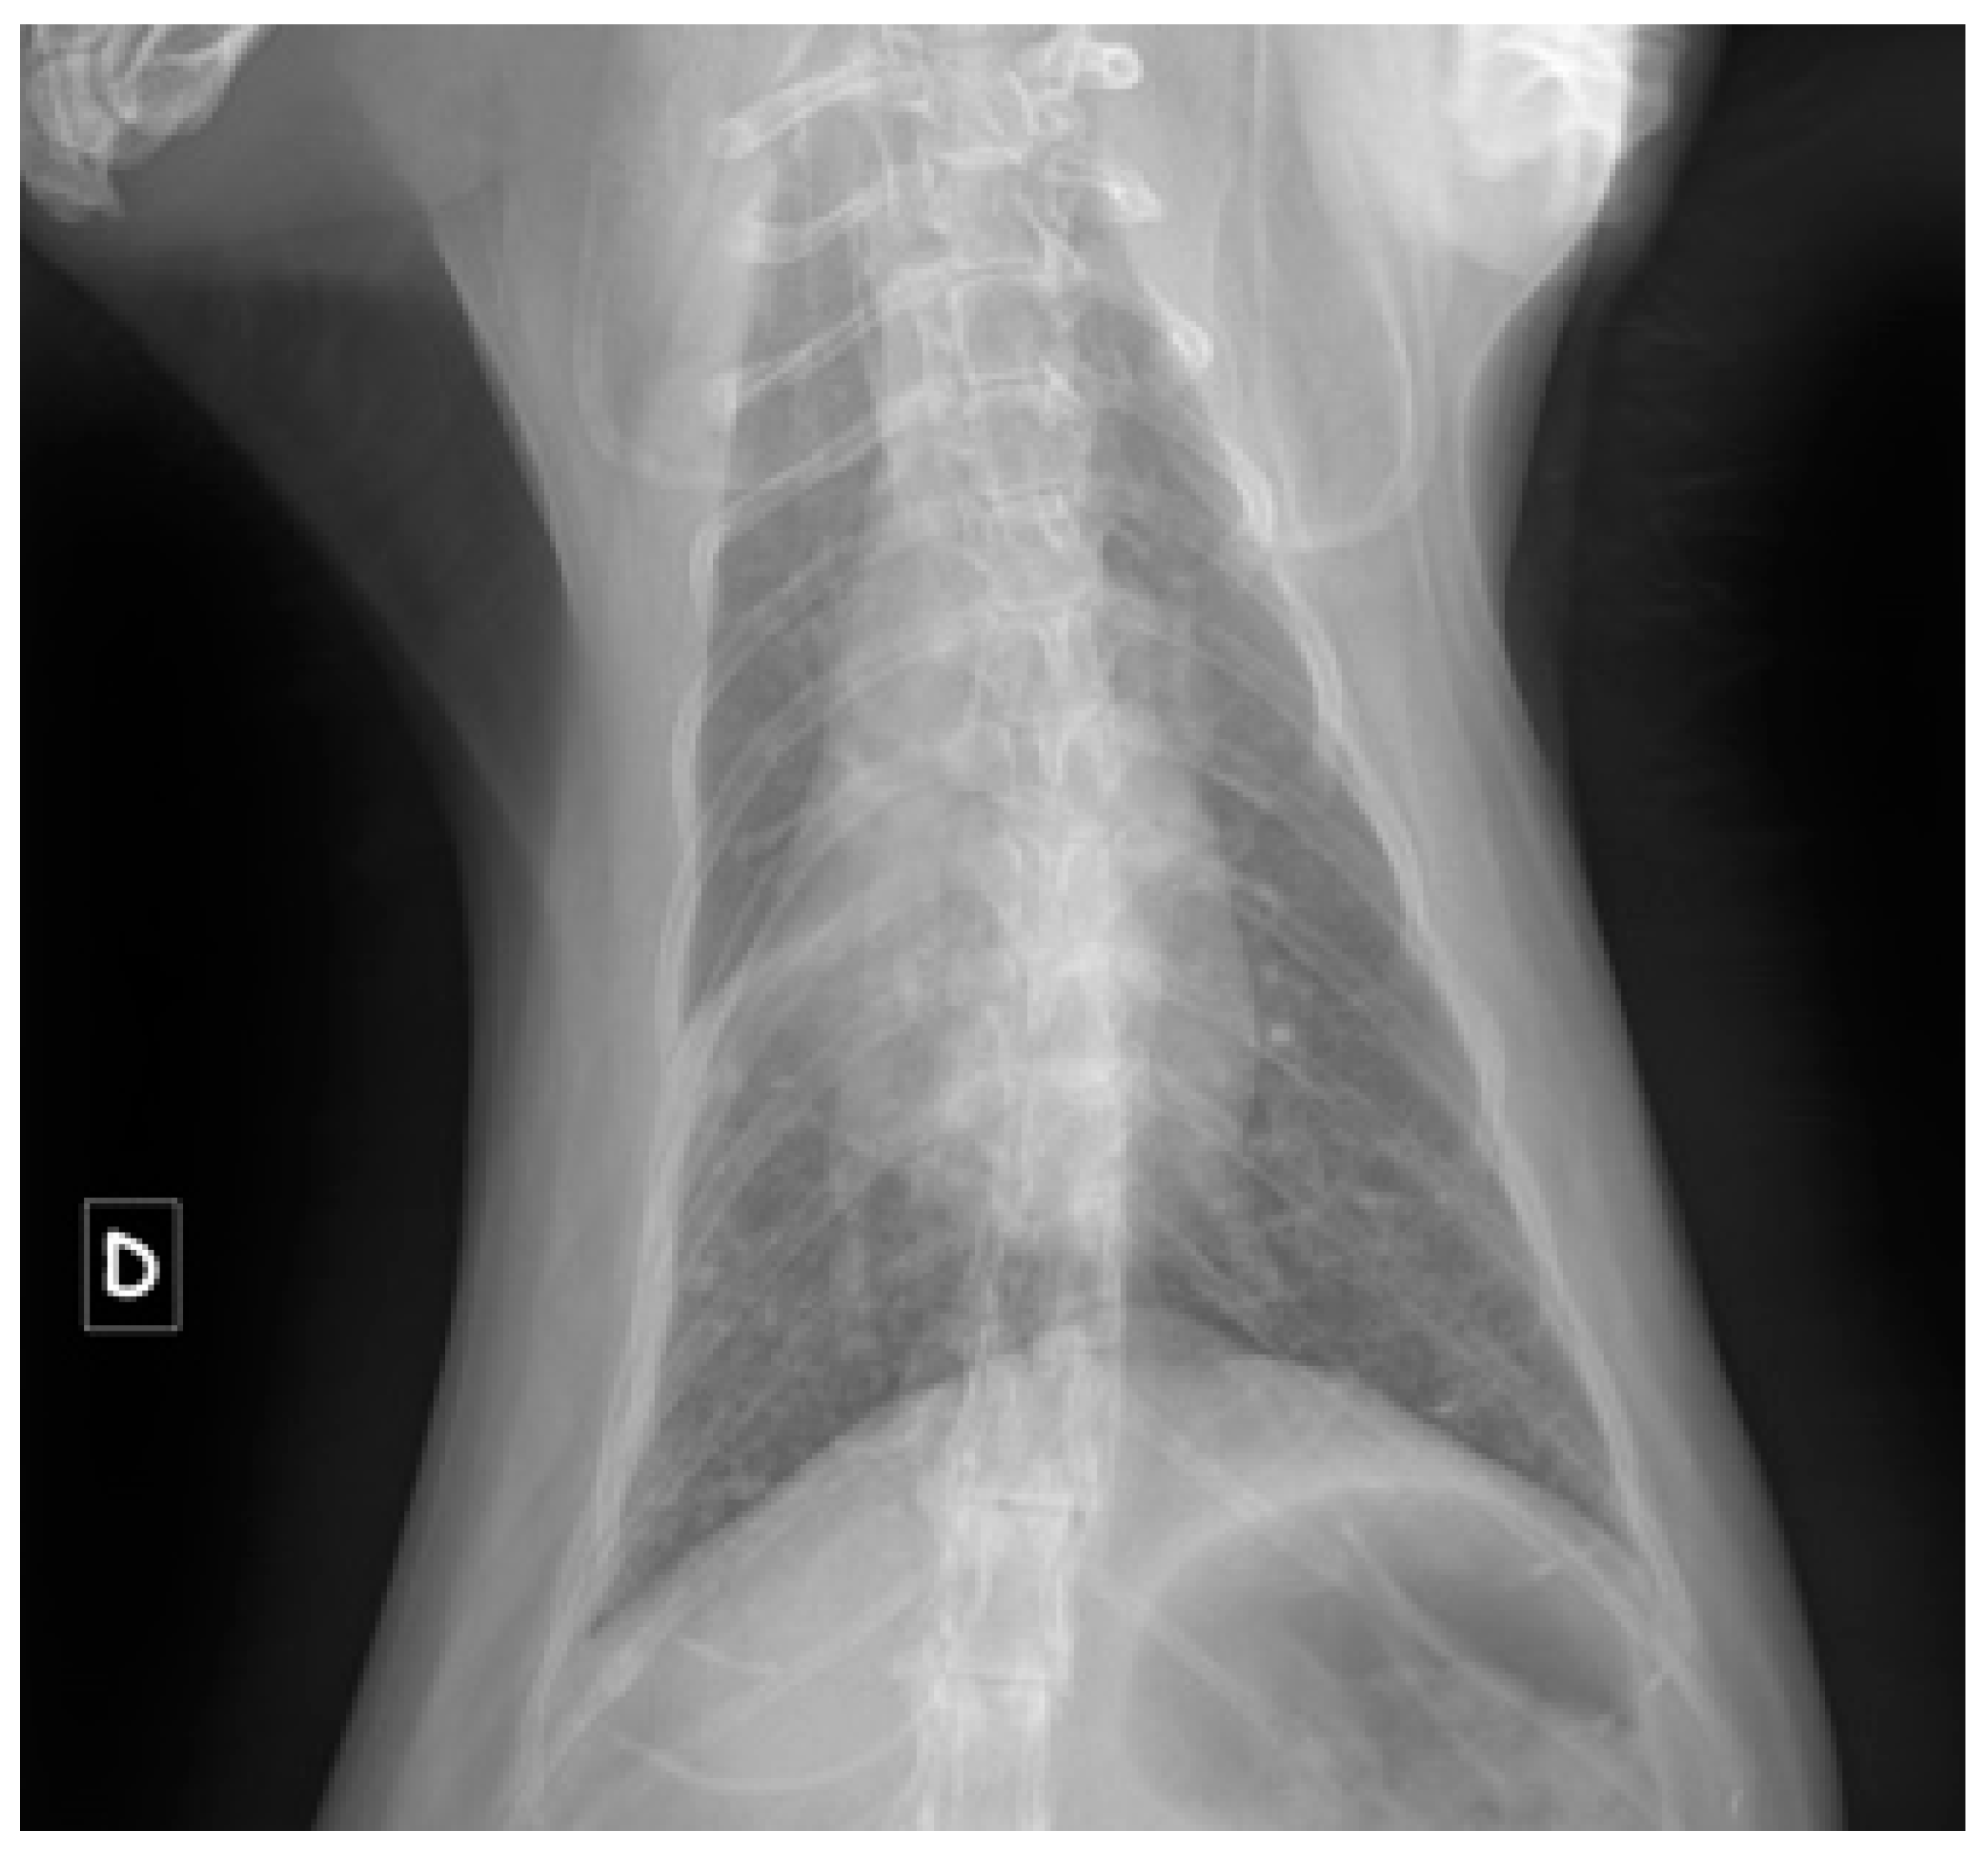

- Pleural effusions